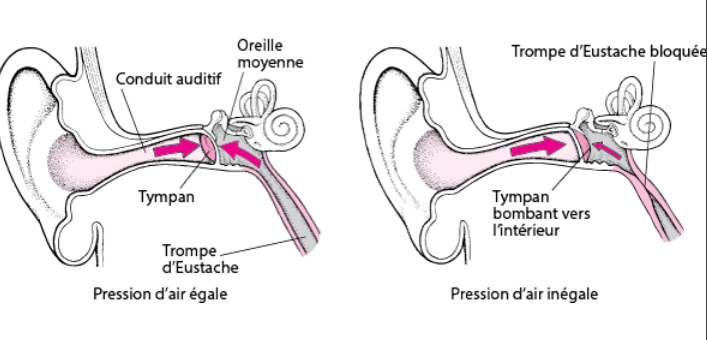

Ici sur cette image, on les voit bien en cas d'otite, c'est bien enflammé. (Les petits traits rouges qui ressemblent à des fils.😉) - Aujourd’hui

D'après mon humble expérience (50 ans de chasse cette année 🥳) le problème c'est la trompe d'Eustache. Je vais peut-être enfoncer des portes ouvertes mais si elle n'est plus perméable pour quelque raison que ce soit les problèmes arrivent*. Perso je ne plonge pas profond ( quasiment tout le temps en dessous de 10m) et j'ai souvent des problèmes pour compenser à la descente au bout d'un certain nombre d'apnées, la plupart du temps impossible de dépasser les 3m. Je patiente, je rince la gorge, je bois un coup...et la plupart du temps l'air repasse enfin, avec quelques gargouillis. C'est un problème qui m'arrive souvent en fin de chasse après une bonne centaine d'apnées. Après la sortie l'audition est un peu "cotonneuse" et je peux avoir des acouphènes. Ça se passe en 1 à 3 jours. Alors, autant un problème de perméabilité à la descente n'est pas dangereux, douleur t'empêchant d'aller plus bas , le blocage à la remontée (comme tu l'as subi toi même) est beaucoup plus problématique car évidemment tu ne peux pas attendre en bas que ton oreille veuille bien te laisser tranquille pour remonter peinard. Ça m'est arrivé une fois, une saison en Bretagne avec des conditions exceptionnelles et (de mémoire) j'ai dû plonger quasiment tous les jours pendant le mois de vacances. C'était (heureusement) pendant l'un des derniers jours, avec les symptômes que tu as décrits, dont l'un est inoubliable, cette douce sensation qu'on t'enfonce un clou dans l'oreille... La nuit suivante, un peu de sang sur l'oreiller, là j'ai flippé quand même. Retour dans mes pénates, rdv ORL au moins 3 semaines après, l' ORL est une espèce en voie de disparition. Il me dit que le tympan est ok , le saignement vient de petits vaisseaux qui on cédé à cause de la distension de la membrane. Le problème c'est qu'à force de faire des apnées la trompe d'Eustache s'enflamme, les parois se collapsent et l'air ne passe plus. Alors évidemment quand on est passionné de chasse et que les conditions sont bonnes on tombe dans le panneau et on "force" un peu sur le physique au lieu de prendre un peu de récupération. Maintenant, le physique n'étant plus ce qu'il était et je suis un peu "contraint" d'espacer les sorties et laisser reposer mes oreilles (et le reste). Je sens quand ça commence à déraper et je me force à attendre que les signes s'estompent avant de me remettre à l'eau, d'autant plus que si je ne tiens pas compte des avertissements un autre problème survient : la sinusite, et là c'est au moins une semaine au sec avec antibiotiques et tout le toutim. Une autre façon de contourner le problème c'est de faire des sorties plus courtes pour éviter de traumatiser ses tympans, ça fonctionne. En bref, pour résumer : il faut écouter ses oreilles ! 😁 *Edit: je viens de voir la réponse de Thearthur.👍 -

Le barotraumatisme de l'oreille moyenne qui semble être celui qui te concerne est effectivement dû à un soucis au niveau de tes trompes d'eustache qui ne laissent pas repasser l'air accumulé lors des compensations. soit leur muqueuse est épaissie à cause d'une inflammation, soit des sécrétions les obstruent partiellement, soit leur forme est impliquée. Une solution est la maneuvre de Toynbee, c'est un valsalva inversé : nez pincé, inspirer et déglutir avec également des mouvements de mâchoire. L'idée est de mettre en dépression les fosses nasales et la cavité buccale pour aspirer l'air des trompes. S'entraîner à sec est sans risque. Se contenter pendant un temps de petits fonds, prendre de la marge pour pouvoir remonter lentement. -

Je n'ai pas de conseil particulier pour lucascmbassin car manifestement il y a un souci physio (voir l'état et la perméabilité des trompes d'Eustache car si le barotraumatisme arrive à la remontée, c'est que l'air ne sort pas). Sois prudent. Une personne de mon club d'apnée vient de se percer le tympan ... en fosse ! Finito l'apnée pour quelques mois au moins. D'une manière plus générale, pour préserver les tympans et éviter de devenir dur de la feuille (un calvaire pour l'entourage si pas équipé), la béance tubaire volontaire (BTV) permet un équilibrage quasi-continu et donc moins traumatique que la manœuvre de Vasalva qui est utilisée trop souvent par à coup et avec des suppressions trop importantes. Penser également à équilibrer dès le canard. On trouve maintenant un paquet d'exercices pour apprendre à maîtriser l'ouverture des trompes d'Eustache. Et quel plaisir d'avoir ses deux mains libres à la descente. -